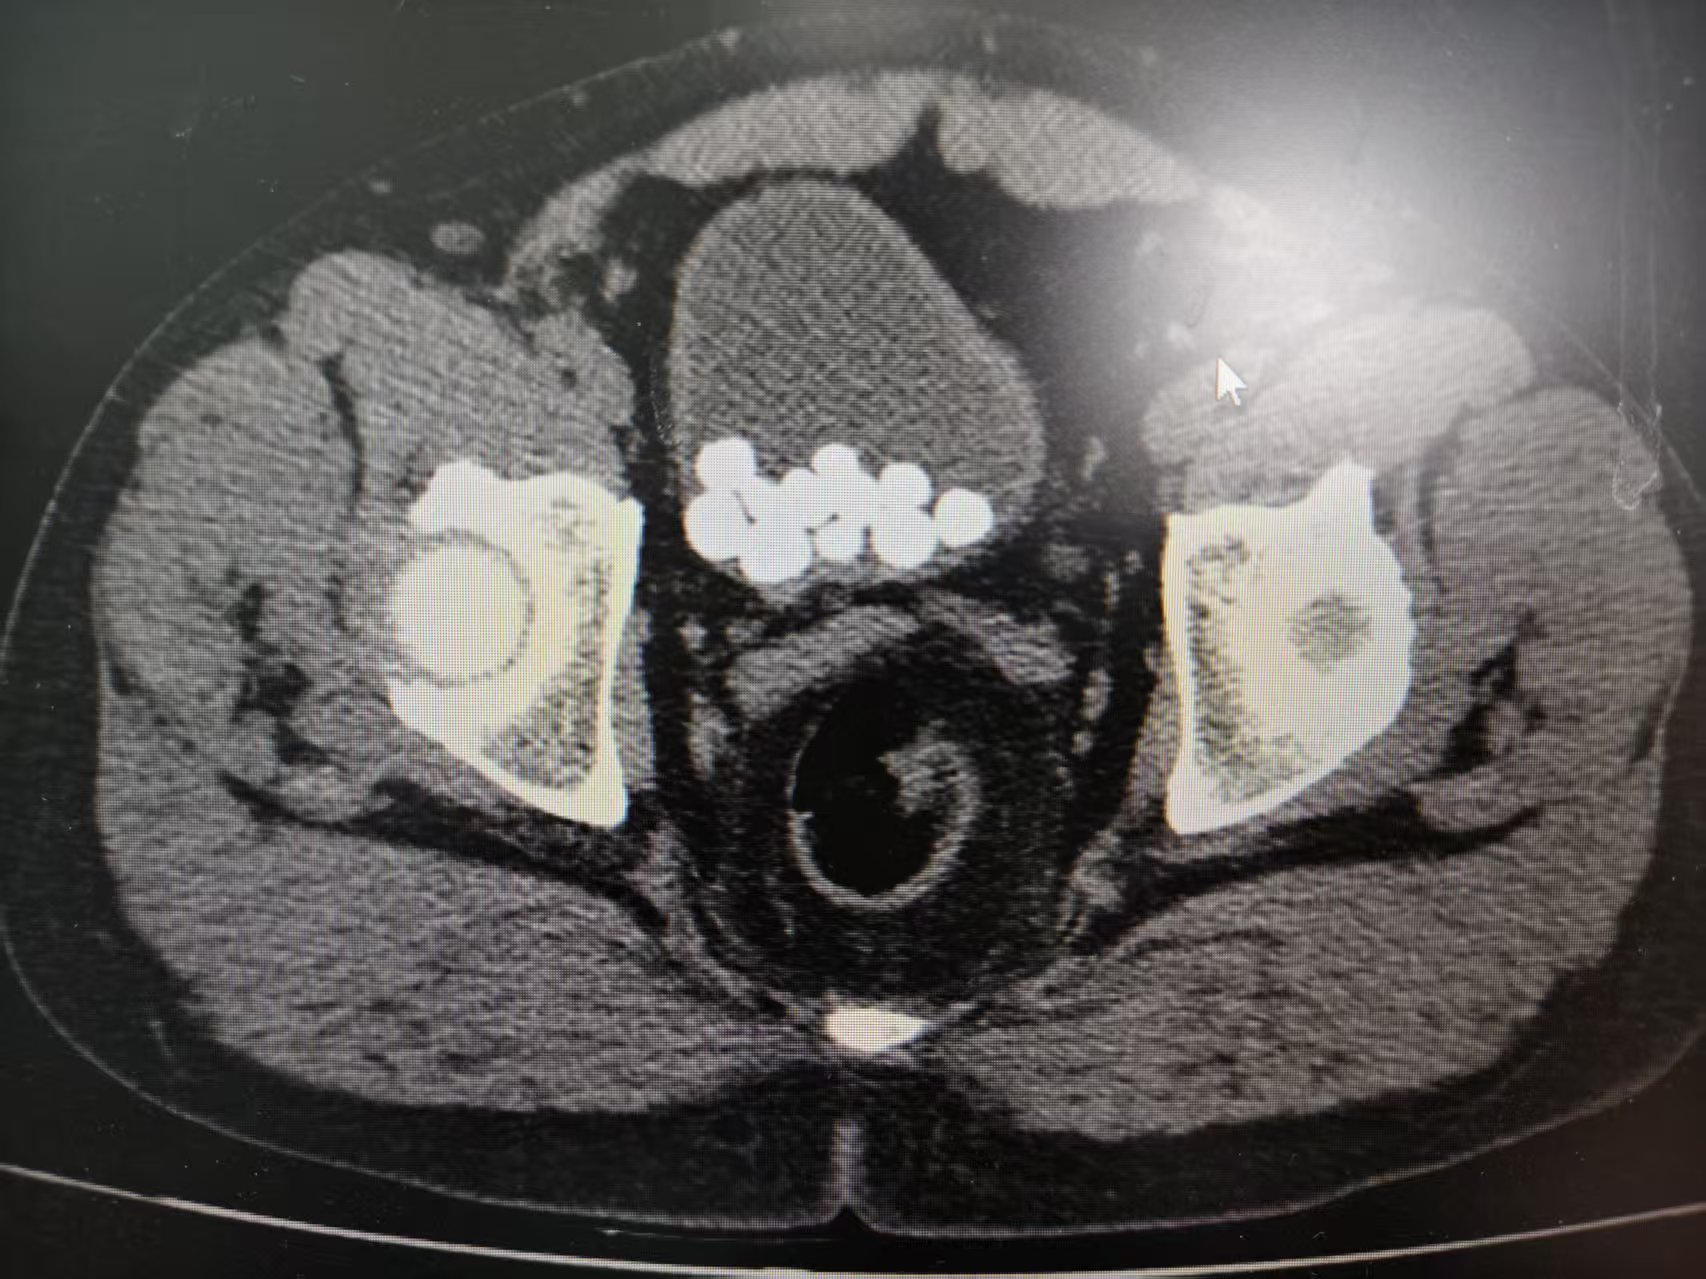

在我院疗养期间,了解到李伯的困境,我们为他安排了相关检查,并确诊其为膀胱结石合并前列腺增生;增生的前列腺压迫尿道导致排尿不畅,尿液淤积形成结石,两大病灶相互影响。

为了让李伯能够尽快恢复高品质生活,我院综合外科专家团队迅速为他制定个性化治疗方案。考虑到李伯年事已高,且膀胱内大量结石,前列腺体积大,团队决定采用微创术式,分次治疗膀胱结石及前列腺增生,一次住院解决两大问题。手术全程通过尿道自然腔道进行,无需腹部切口,专家精准激光碎石技术将膀胱结石击碎并取出,切除增生前列腺组织,整个过程顺利,出血量少。